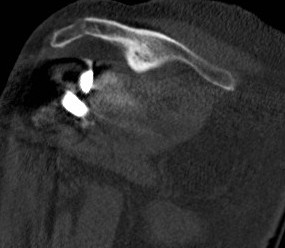

Acromial stress fracture

Acromial stress fracture on xray